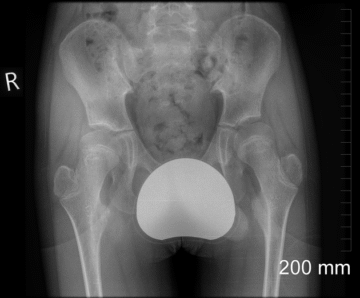

اعوجاج العمود الفقري الناتج عن مشاكل الفخذ والحوض عند الأطفال: الأسباب والعلاج…

اعوجاج العمود الفقري الناتج عن مشاكل الفخذ والحوض عند الأطفال: الأسباب والعلاج يُعد اعوجاج العمود الفقري من أكثر الحالات التي تُقلق الأهل، خصوصًا عندما يظهر في سن الطفولة أو المراهقة دون سبب واضح. كثير